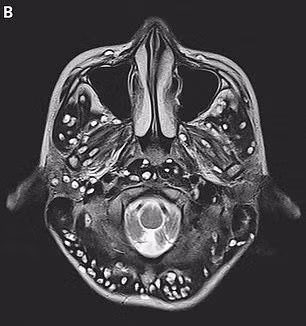

Qua kết quả quét não MRI, bác sĩ nhận thấy có rất nhiều trứng sán ở khắp vỏ não, mắt phải và tinh hoàn phải.

Bác sĩ xác định cậu bị bệnh u nang thần kinh học, được Tổ chức Y tế Thế giới (WHO) định nghĩa là "nhiễm ký sinh trùng ở hệ thần kinh trung ương và do sán lợn Taenia solium gây ra".

Căn bệnh này xảy ra do một loại sán dây có trong thịt lợn, đặc biệt là thịt lợn không được nấu chín, xâm nhập vào cơ thể và "làm tổ" tại não.

Neurocysticercosis là một dạng nhiễm trùng bởi các u nang do ấu trùng của sán dây lợn tạo ra. Đây là những túi chứa ký sinh trùng chưa trưởng thành. Những u này có thể ảnh hưởng đến những bộ phận khác nhau của cơ thể. như hệ thống thần kinh trung ương, cơ, da và mắt.

Khi chúng hình thành trong não được gọi là Neurocysticercosis. Não bị ảnh hưởng có thể gây ra co giật và tử vong. Mức độ tổn thương não trong trường hợp này được so sánh ngang với u xơ thần kinh.